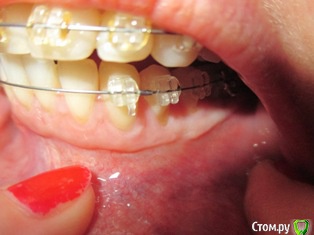

Наталья1 Опубликовано 30 марта, 2017 Автор Поделиться Опубликовано 30 марта, 2017 1) Первые 2 фото - левый нижний сегмент после операции,2) 3 следующих фото - правый нижний сегмент без операции ( требуется ли? ИМХО, разница в высоте прикрепления десны незначительная, а какие последствия на лице!), 3) последнее фото - последствия на лице ( залом на щеке). Ссылка на комментарий

Наталья1 Опубликовано 31 марта, 2017 Автор Поделиться Опубликовано 31 марта, 2017 Залом на щеке и как-будто она в складку валиком собралась. Всё это произошло после установки брекетов на нижнюю челюсть. Т.е. Вы в практике сталкивались с случаями восстановления тонуса? А нужна ли была вообще вестибулопластика , как считаете? Ссылка на комментарий